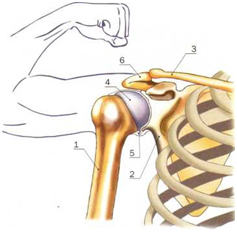

Диаграммы и схемы движения в суставах человека